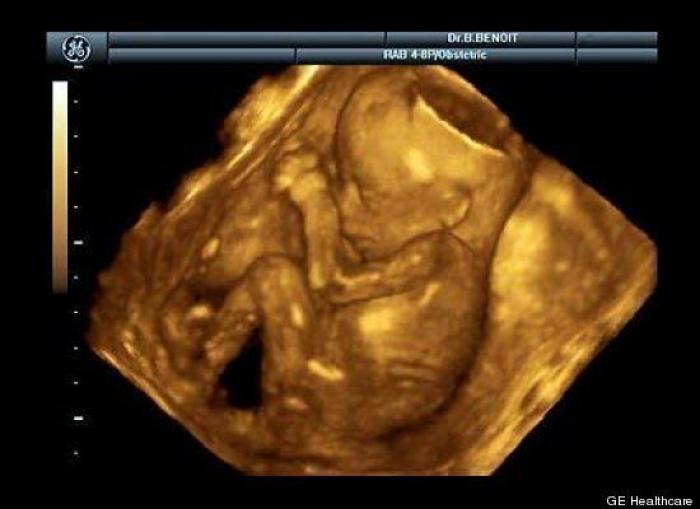

En esta galería puedes ver en fotos como es el desarrollo de un feto de semana en semana:

Desarrollo del feto, en fotos

Ver la galería